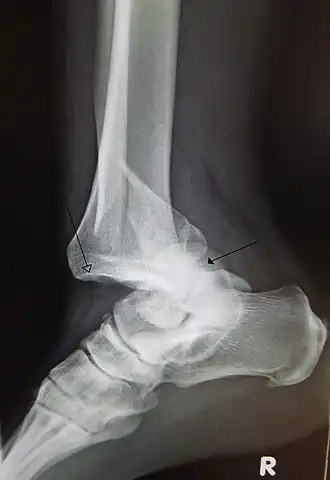

Перелом нижней трети правой малоберцовой кости со смещением и вывихом стопы кзади